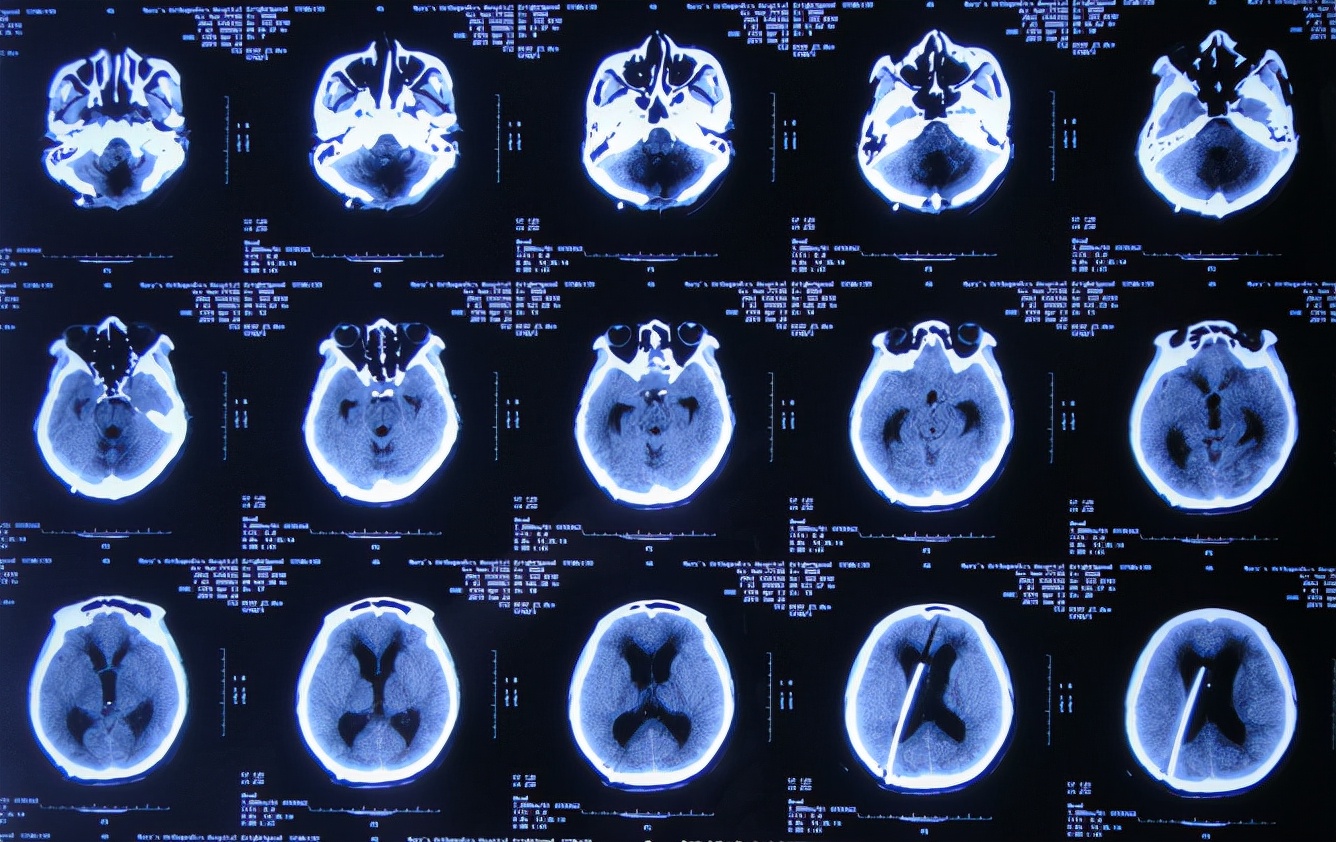

患者2019年2月18日下午,睡觉时突然出现剧烈头痛,持续无缓解,于是就诊于当地的山西省文水县某医院,查头颅CT示小脑出血破入脑室( 图-1 );考虑出血量不多,住院保守治疗。

图-1: 2019年2月18日头颅CT

但1小时后出现意识障碍加重,复查头颅CT( 图-2 )示小脑出血增多,急诊进行了左侧脑室穿刺外引流术+后颅窝血肿清除;术后住入重症监护室。

图-2: 2019年2月18日头颅CT02